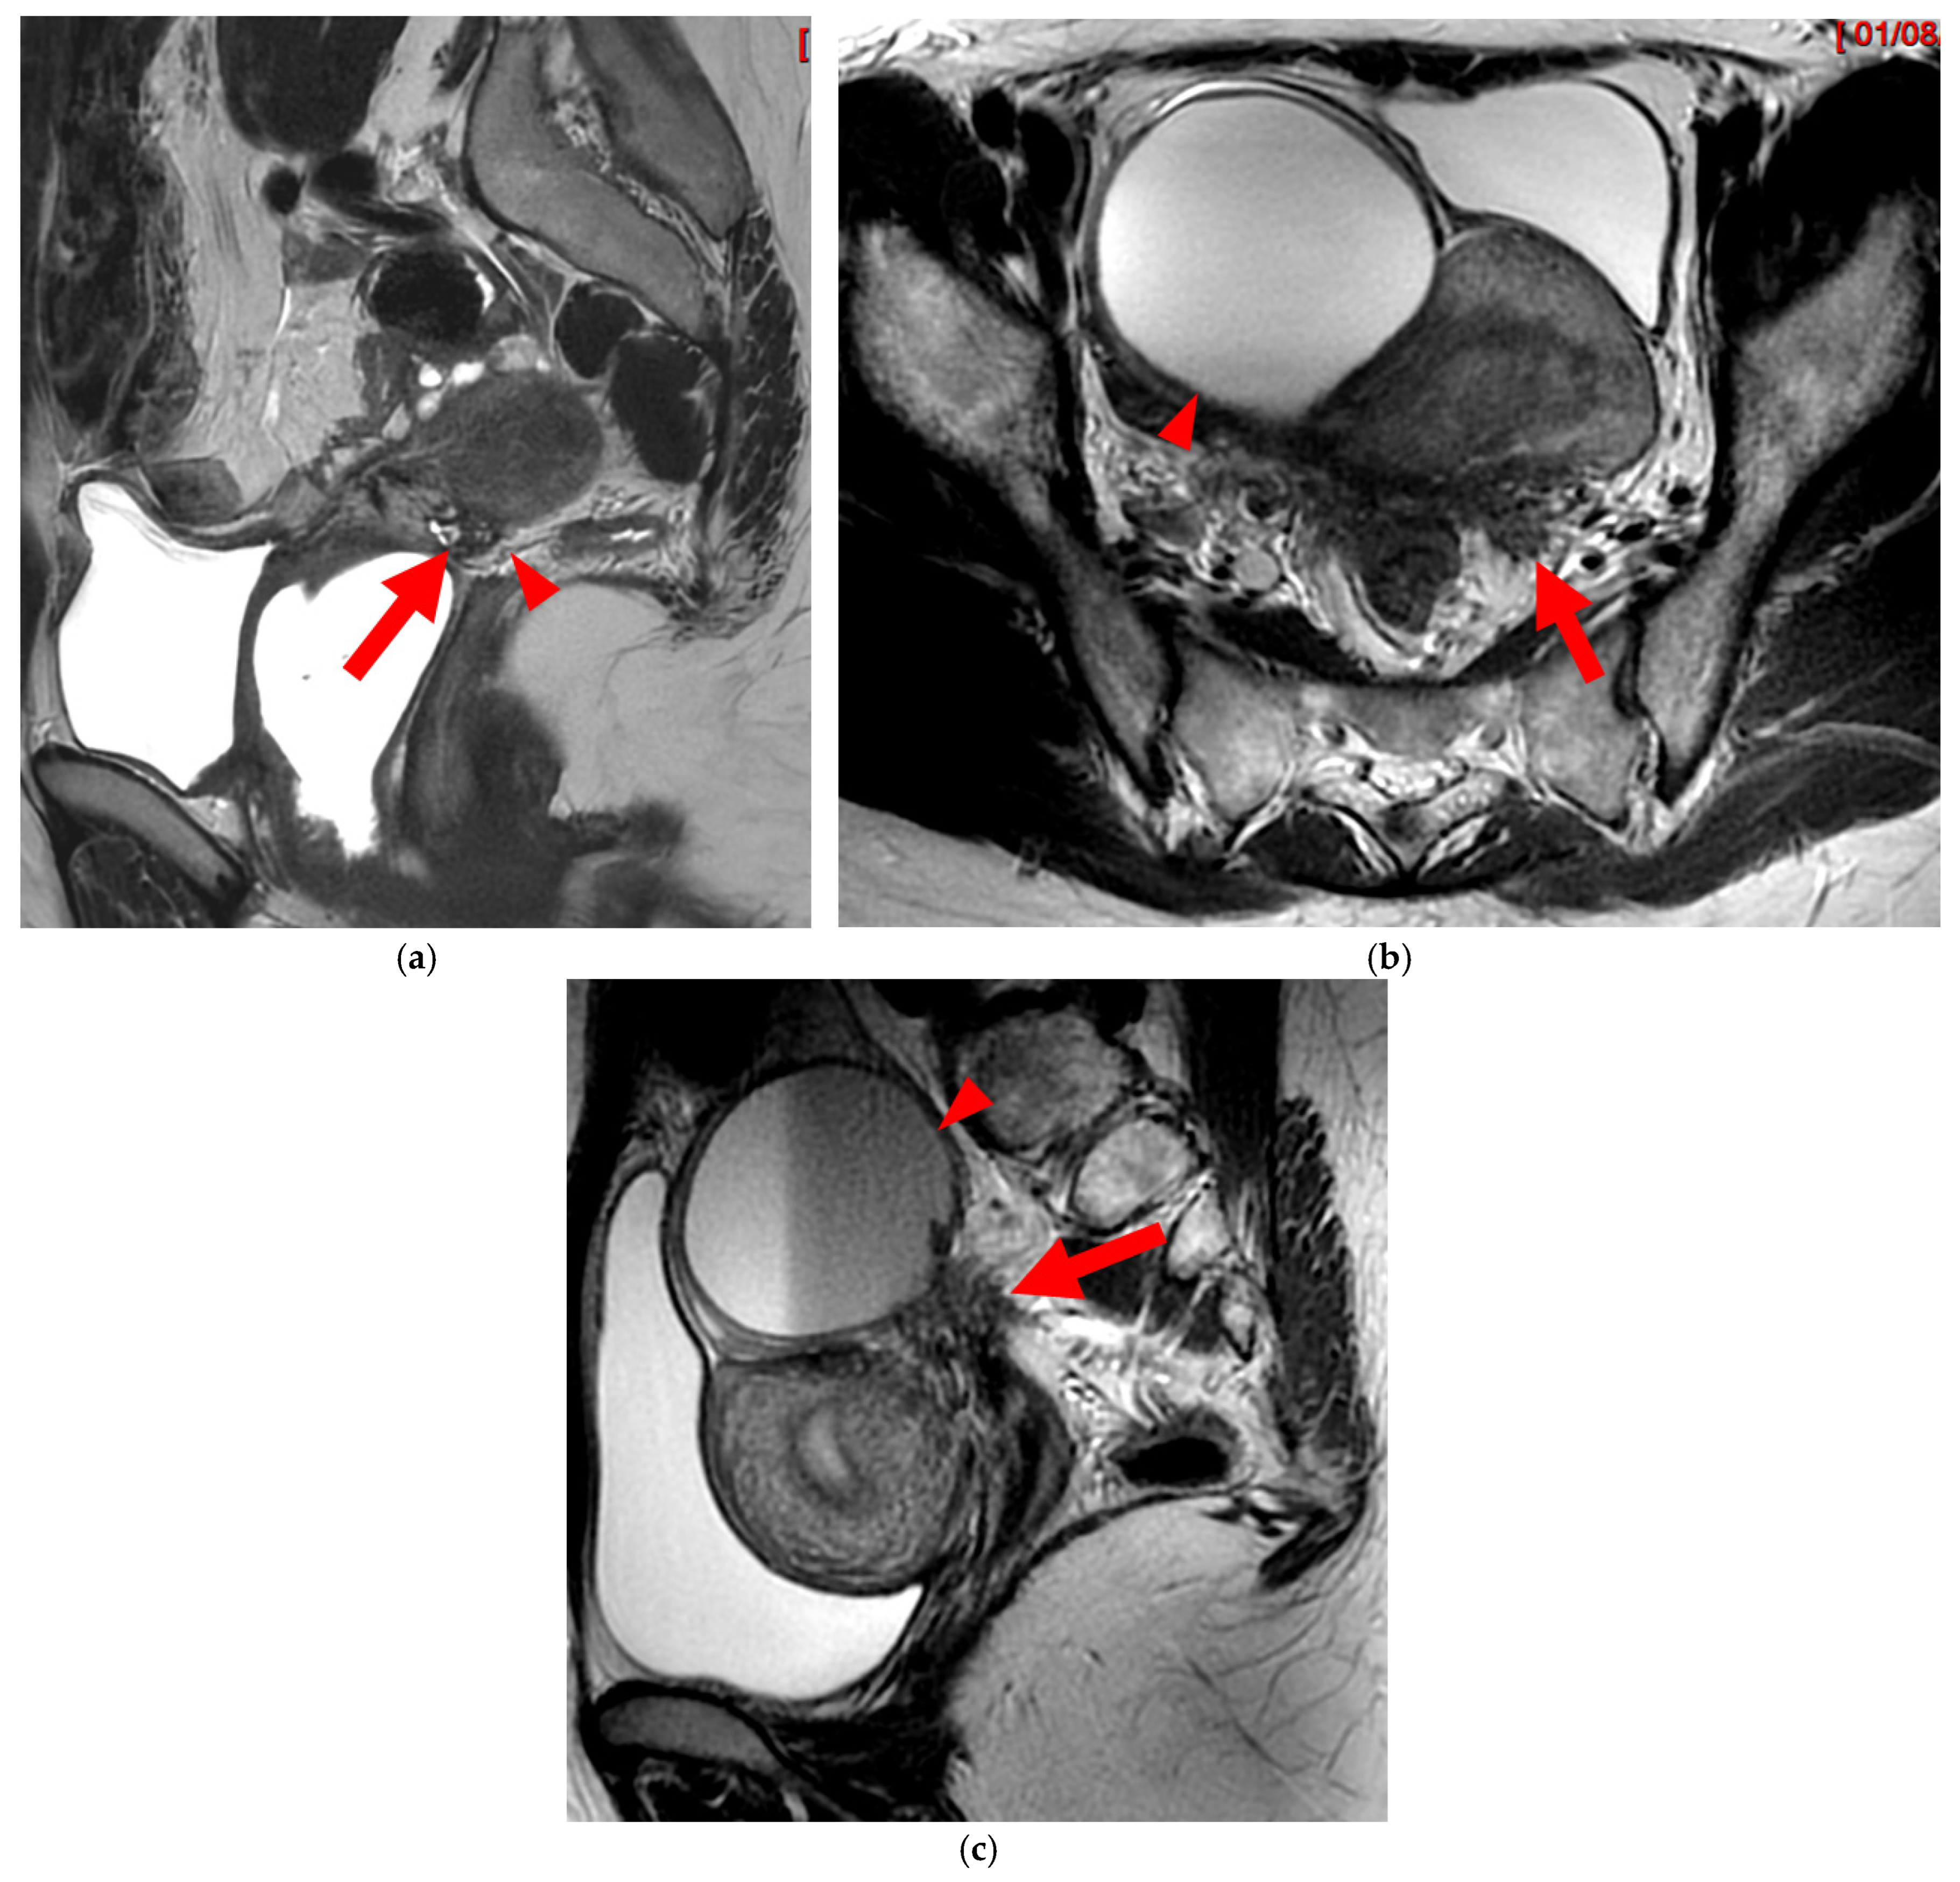

Figure 6. Pelvic MRI scans of two patients with HTD type 5A USLs. (a,b) Sagittal T2WI: nodularity with regular margins (arrows) within the right USL (arrowheads).

A type 5A USL (Figure 6) is nodular with a smooth contour.

Figure 7. Pelvic MRI scans of two patients with HTD type 5B USLs. (a) Patient 1: sagittal T2WI shows a microcystic nodule (arrow) within the origin of the right USL (arrowhead). (b,c) Patient 2: axial (b) and sagittal (c) T2WI show a nodular left USL with spiculated margins (arrow) and a right ovarian endometrioma (arrowhead).

A type 5B USL (Figure 7) is nodular with spiculated margins. A type 5B USL may also display an isolated nodule with microcystic content.